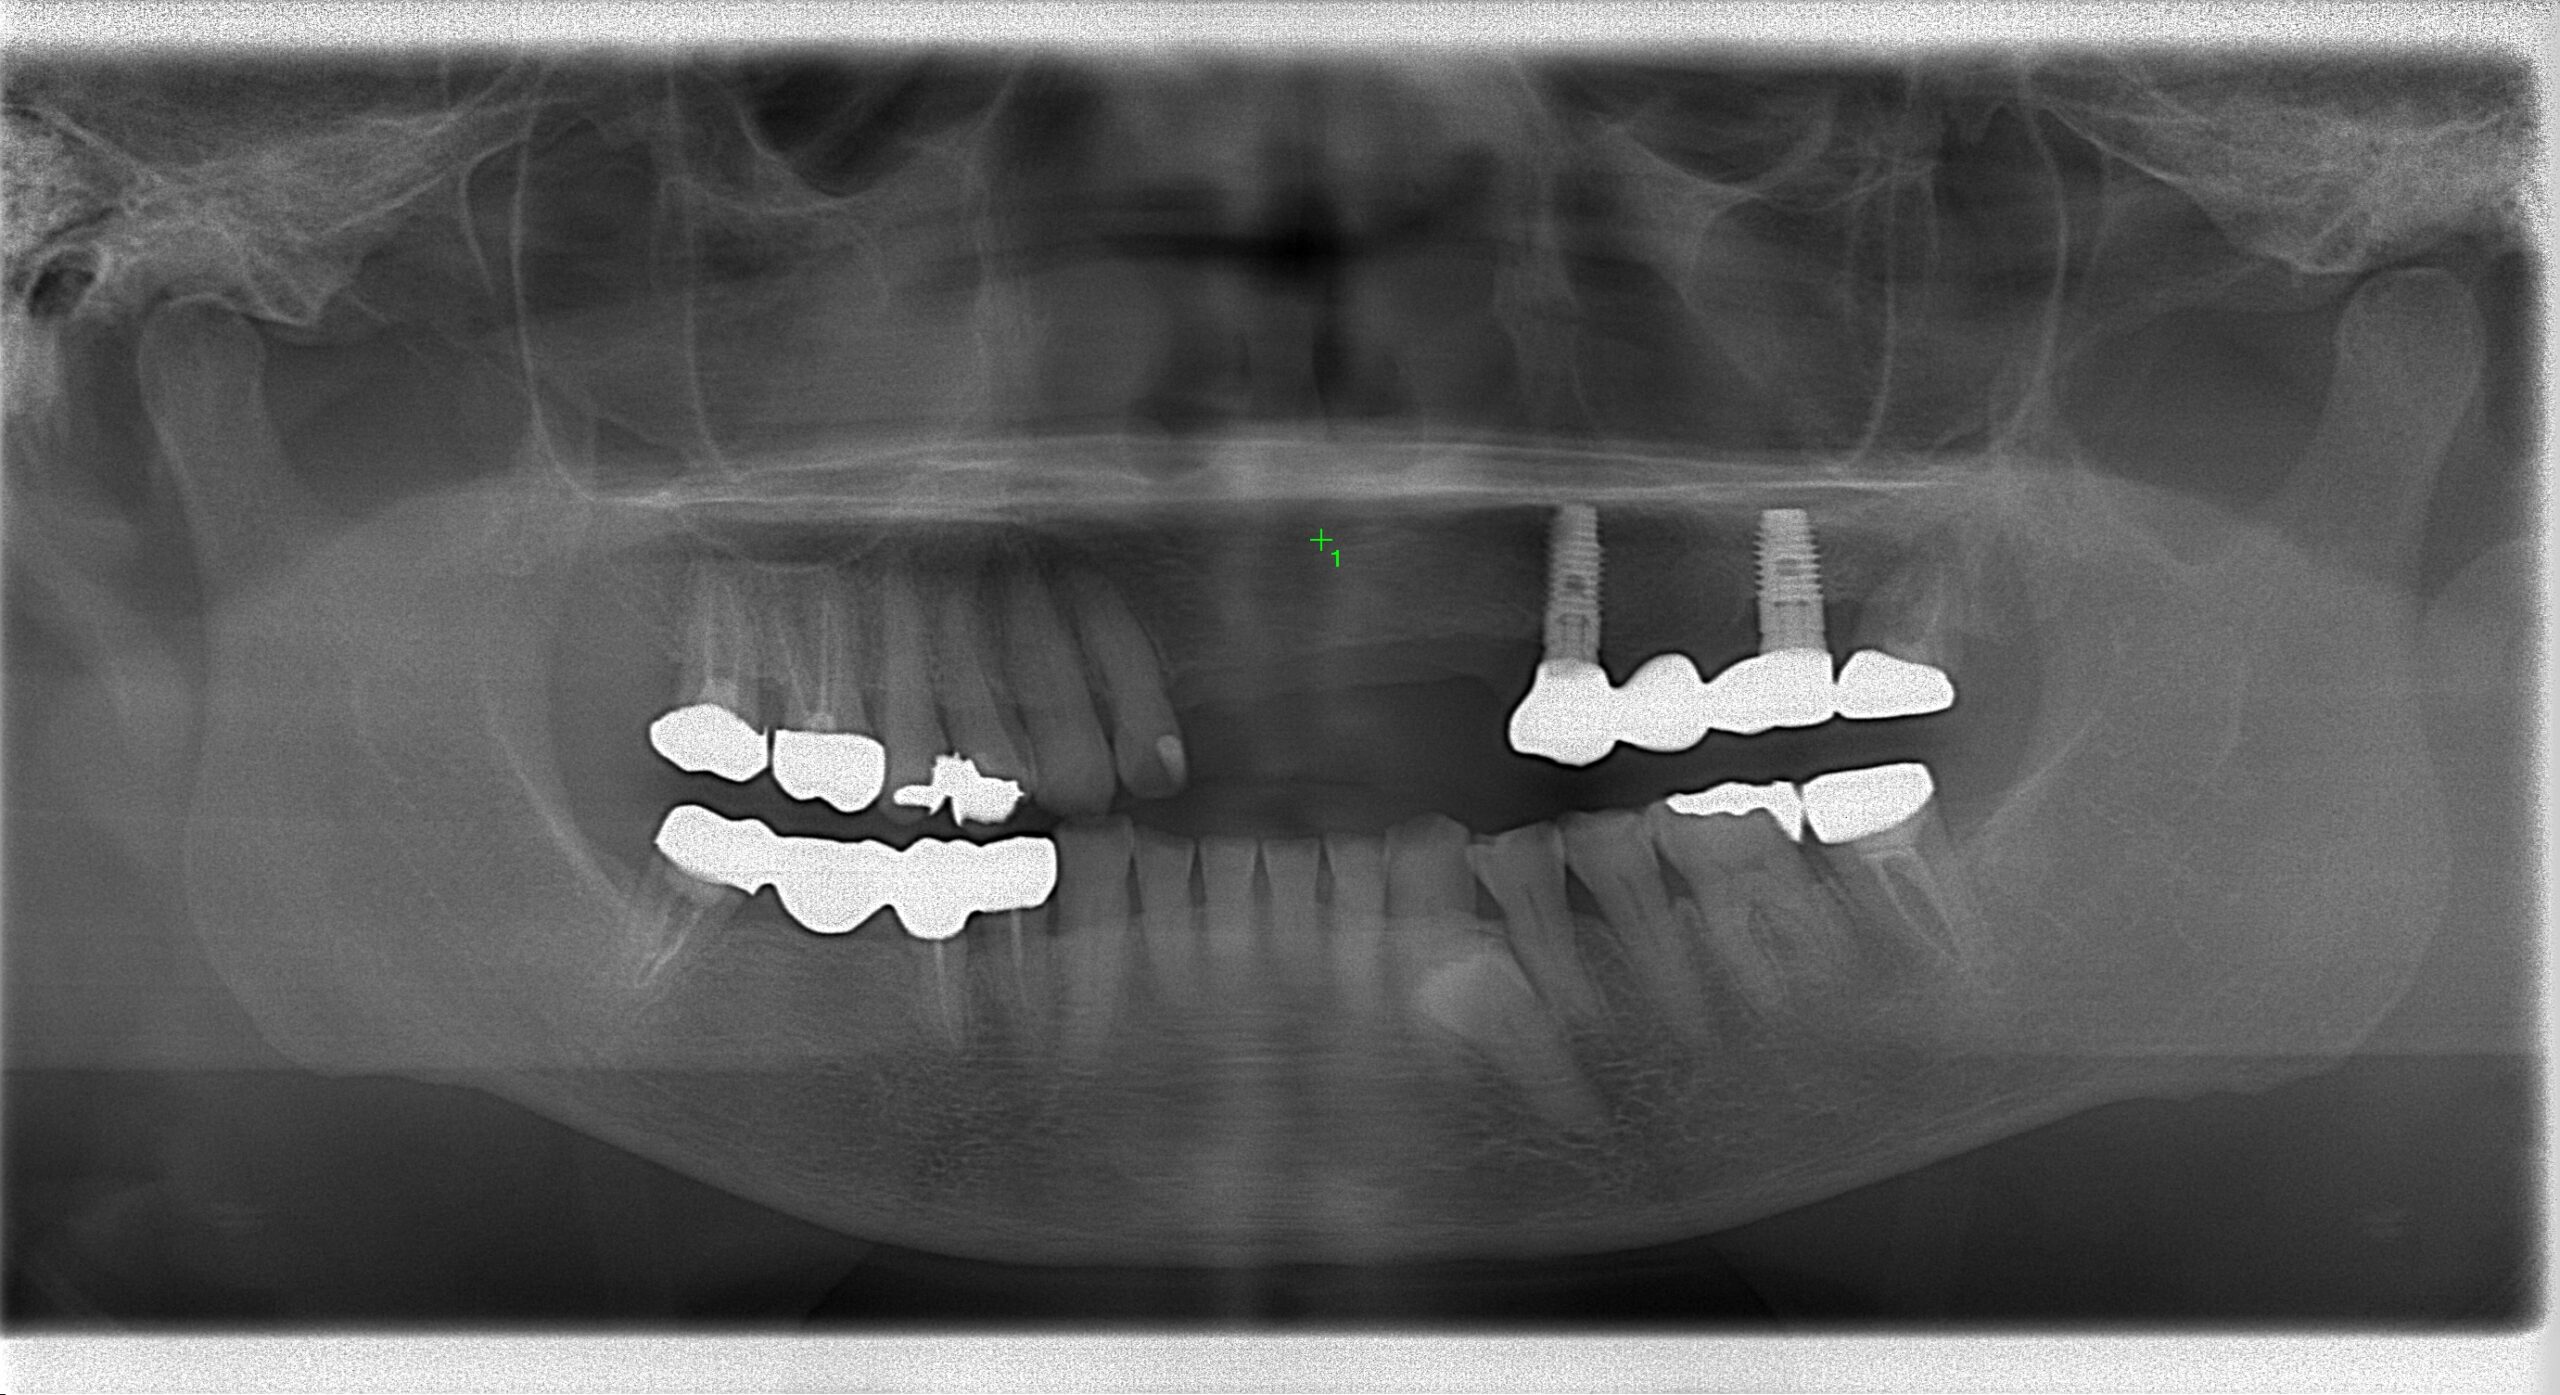

治療前